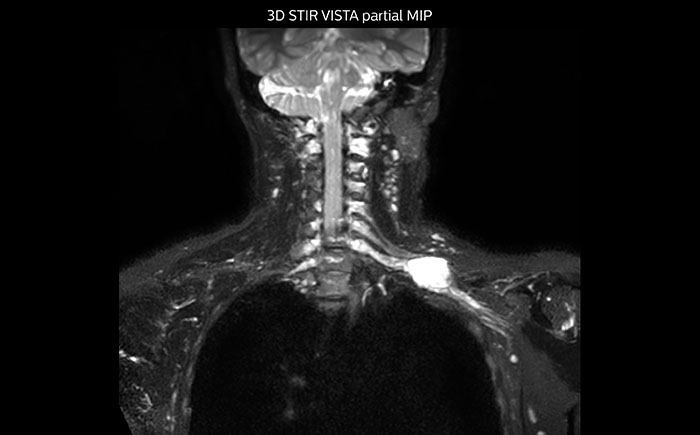

This patient is a 43-year-old female with a left supraclavicular nerve sheath tumor. The lesion is well visualized on the STIR VISTA images and on the MR neurography using DWIBS. The exam was performed on Prodiva 1.5T.

Acq voxel size 1.2 x 1.3 x 2.4 mm, Recon voxel size 0.7 x 0.7 x 1.2 mm, dS SENSE factor 2, scan time 5:46 min.